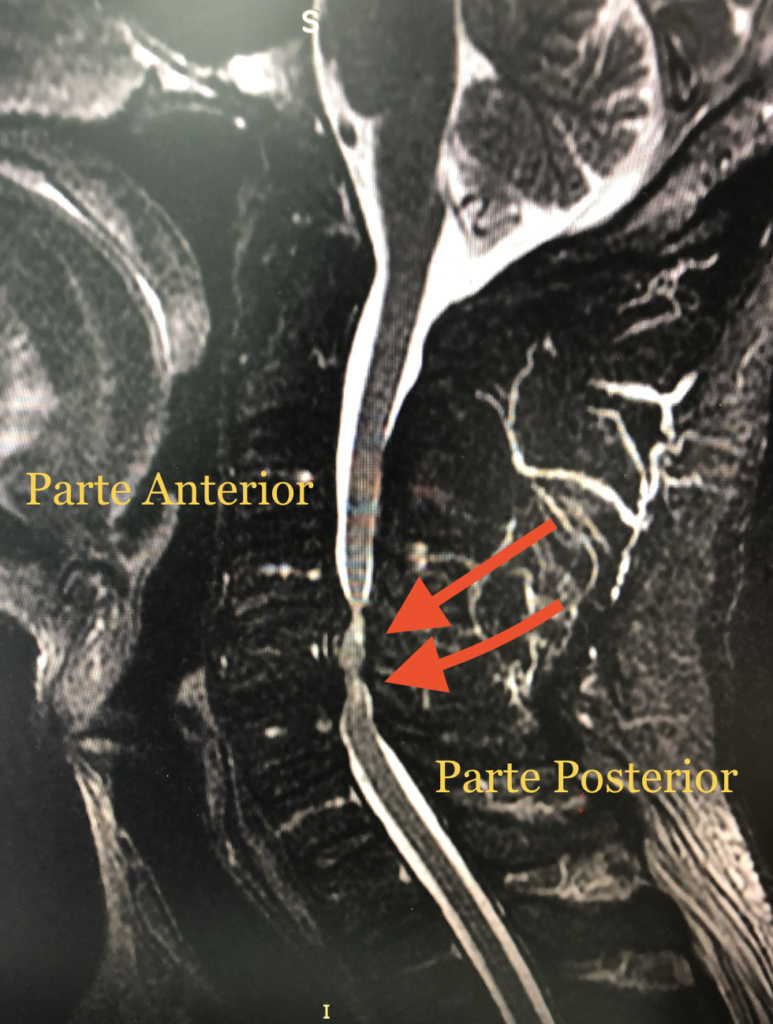

En la resonancia magnética cervical se dan cuenta que tiene dos hernias discales muy grandes que comprime la médula y la tiene ya parcialmente parcialmente dañada.

Esta es una resonancia magnética, donde las flechas rojas Ubican 2 a de compresión severa de la médula. En este caso se decidió hacer una cirugía por Via Anterior, para quitar una vértebra completa y poder hacer una descompresión amplia y segura.